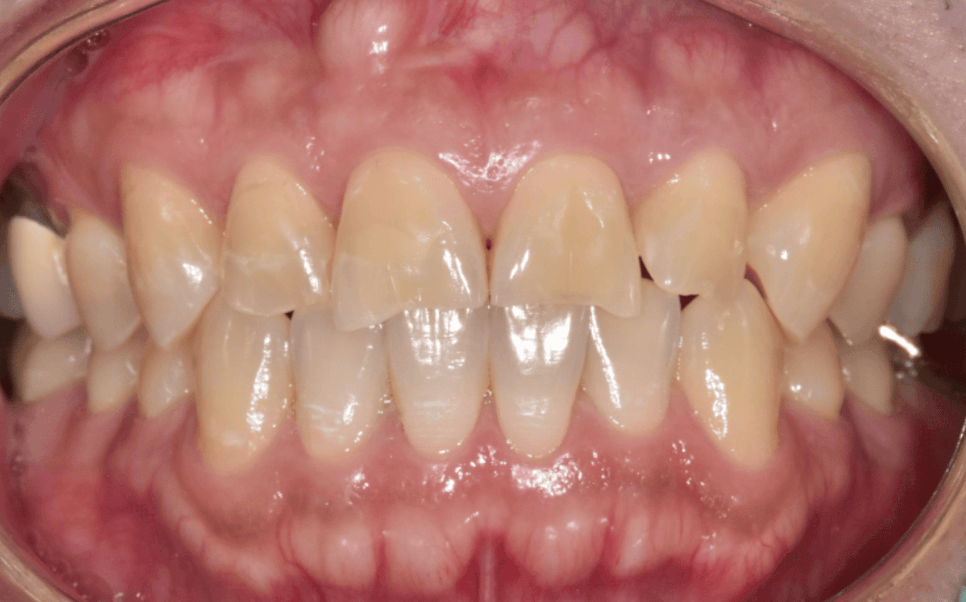

이 환자분은 앞니로 꽃게를 드시다가

앞니 끝(절단은)이 깨져 내원하셨습니다.

사진과 검사상 다행히도

신경이나 뿌리까지 금이 이어진 흔적은

보이지 않았습니다.

교합을 확인했을 때도

위 앞니가 아래 앞니를 살짝 덮는

정상 범주의 교합이어서,

레진으로 수복하더라도

쉽게 다시 깨질 가능성은 높지 않은 상태였습니다.

그래서 내원한 당일에 레진으로

자연스럽게 앞니 형태를 회복해 드렸습니다.

환자분도 깨지기 전 모습 그대로 돌아온

앞니를 보시며 안도하시는 표정이셨습니다.

이 환자분은 1세대 실손보험을 가지고 계셨고,

치아파절 실비 청구가 가능한 상황이었죠.

그래서 필요한 서류를 제출하실 수 있도록 안내드렸습니다.

결과적으로 비급여인 앞니 레진 치료 비용까지

보상을 받으실 수 있었습니다.